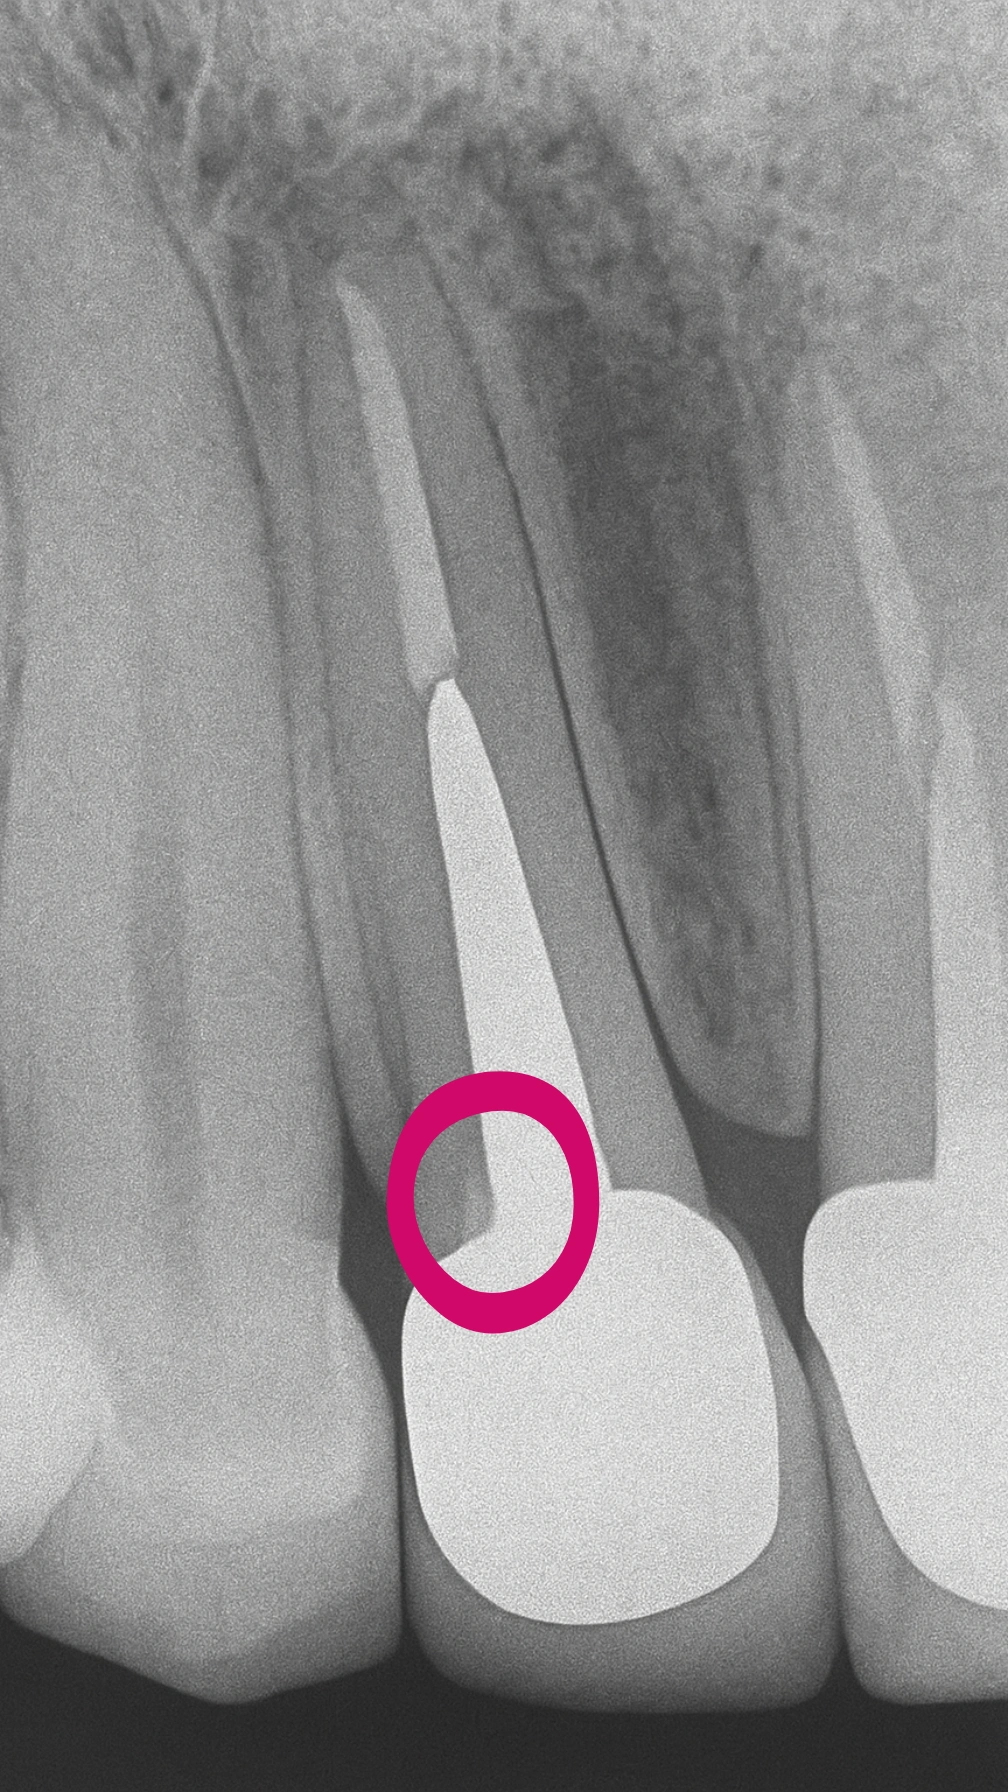

در دندانهای قدامی درمانشدهٔ اندو، پس از تراش و آمادهسازی، گاهی یکی از دیوارهها بهصورت نازک و کاسهمانند باقی میماند. طبق اصول کلاسیک پروتز، چنین دیوارهای نمیتواند فرول مؤثر ایجاد کند، زیرا ضخامت کمتر از یک میلیمتر در برابر نیروهای کششی و خمشی دوام کافی ندارد.

از سوی دیگر، کوتاهکردن یا حذف این دیواره برای تأمین ضخامت، در ناحیهٔ قدامی باعث افت زیبایی و کاهش طول کلینیکی میشود — و دندان را میان دو انتخاب دشوار قرار میدهد: حفظ نسج یا تأمین فرول.

در این کیس، با تکیه بر همان فلسفهٔ بیومیمتیک و قدرت باند بالای آن و با توجه به محدود بودن نازکی دیواره فقط به یک دیواره،

- بهجای کوتاهکردن دیوارهٔ ضعیف، تصمیم گرفته شد آن دیواره بازسازی و تقویت شود تا بتواند عملکرد خود را بهعنوان بخشی از ساختار دندان بازیابد.

- پایداری عملکردی: به این ترتیب، دیوارهای که از نظر کلاسیک برای فرول مناسب نبود، بهصورت بیومیمتیکی و عملکردی به نسج دندانی متصل شد و نقش خود را در ایجاد پایداری کلی ایفا کرد.